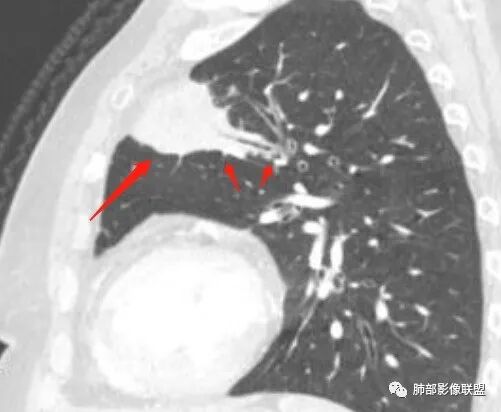

1、坏死区环形强化,指向慢性脓肿。

2、坏死区有血管,基本排除结核。

3、这个卫星灶,更进一步定了大方向,炎性。

※综上所述,看到这四幅图,基本能够准确诊断炎性※